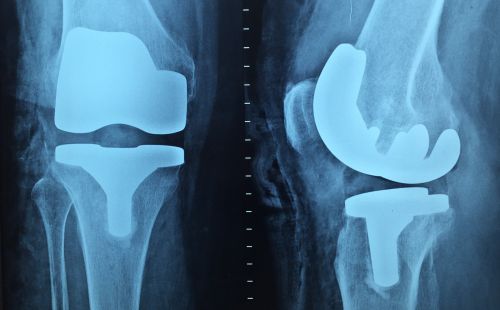

- What type of implant will you use?